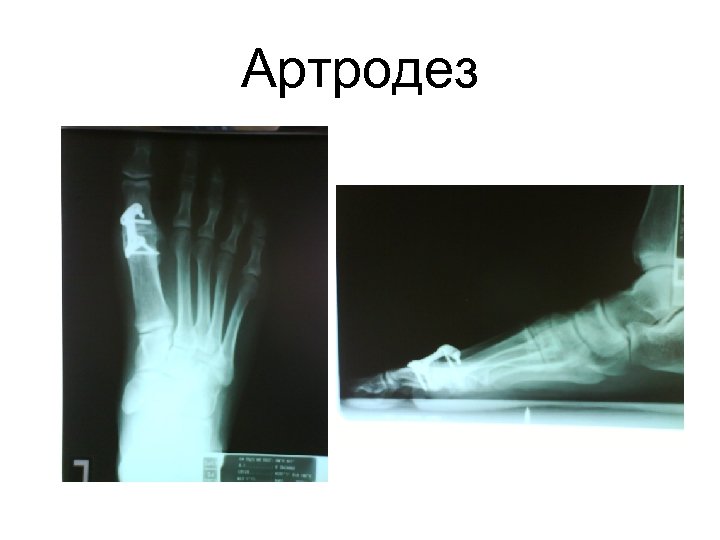

Ригидусная патология большого пальца • Артродез ( используя новейшие техники фиксации) • Разгрузка сустава. Ригидусная патология большого пальца • Артродез ( используя новейшие техники фиксации) • Разгрузка сустава. • Ендопротезирование 1 метатарзо фалангеального сустава ( Total Toe Replacement)

Артродез Артродез